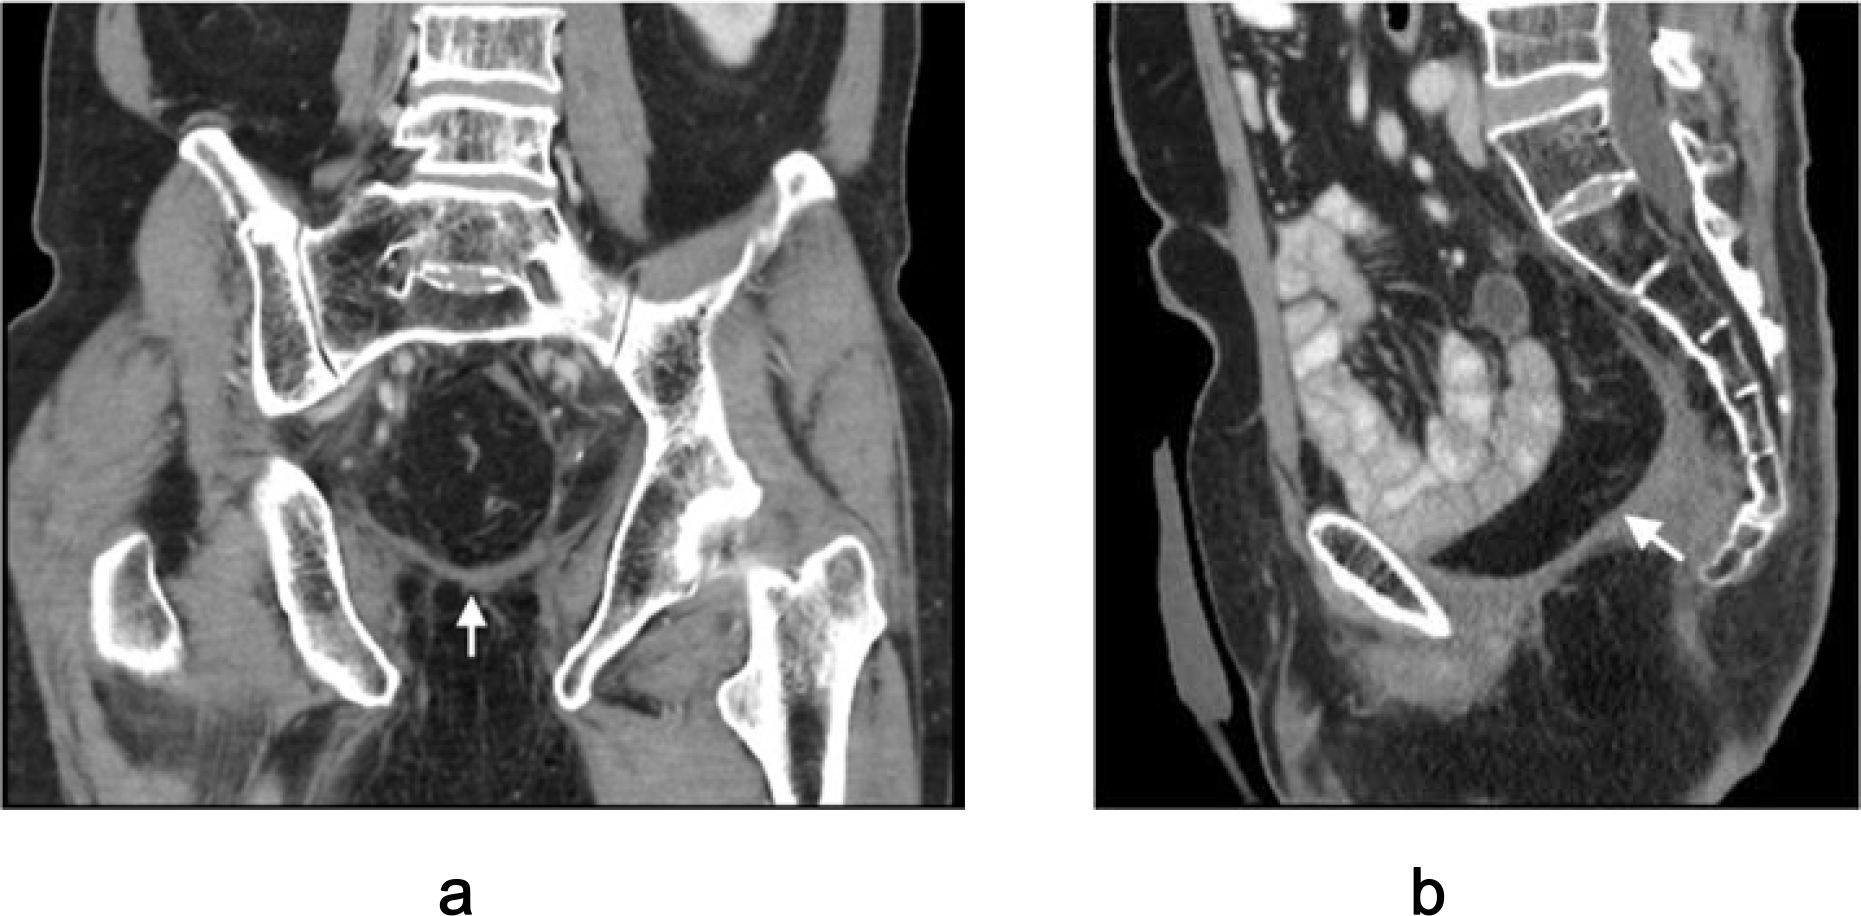

For female patients undergoing APE with en bloc vaginectomy, the mucosa-intact sigmoid flap mimics the natural vaginal environment (Figure 1).

Figure 1. Mucosa-intact colonic flap for neovaginal reconstruction. (a) Spatulation of the sigmoid colon along the anti-mesenteric border. (b) Anastomosis of the flap to the remnant anterior vaginal wall, forming a self-lubricating neovagina.

Advantages: The colonic mucosa provides self-lubrication, maintains luminal width and depth, and avoids the dryness, keratinization, and irritation seen with skin flaps (4). This translates into improved sexual function and patient satisfaction.